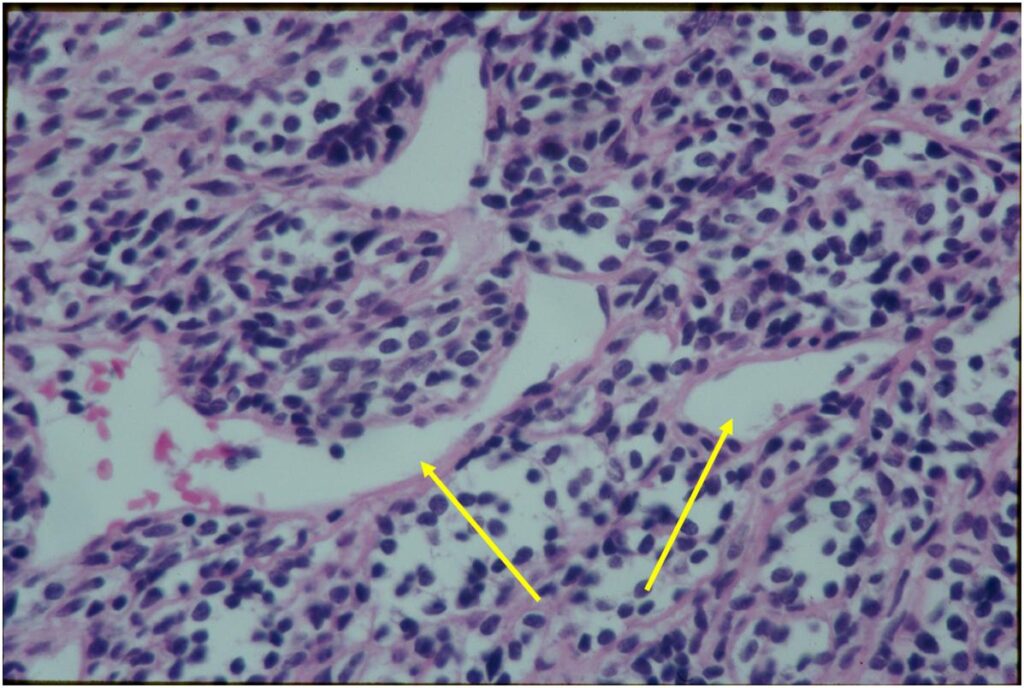

- Lesions are vascular and often have large, anastomosing vessels that impart hemangiopericytoma-like pattern

(Right Arrow) Cartilaginous Component